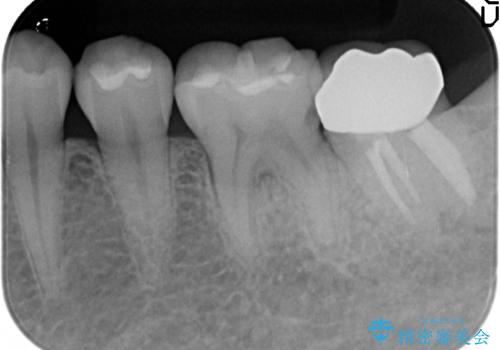

オールセラミッククラウンについて

今回用いたオールセラミッククラウンはジルコニアフレームという白い素材の上にセラミックを盛っているため、審美性が非常に高いのが特徴です。

また、ジルコニアは人工ダイヤモンドの材料にも使われているほど高い強度を持っており、そのためオールセラミッククラウンは審美性だけでなく、奥歯やブリッジの補綴も可能とするクラウンです。